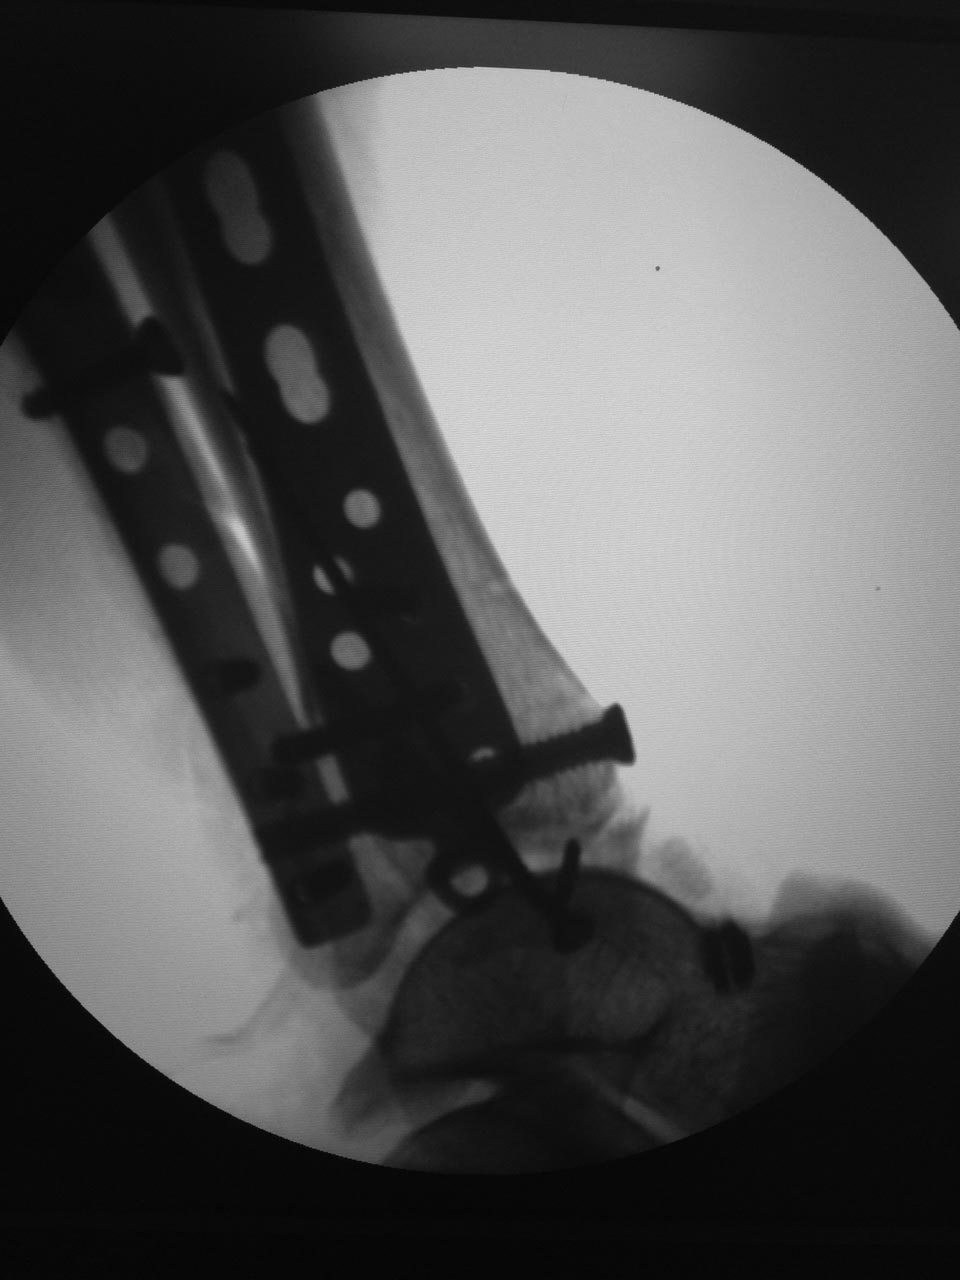

[Ortho] Травма голеностопного сустава 44С3 помогите определиться с оперативной тактикой

Результат.